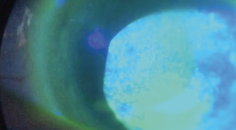

Fortunately, the toolbox of aesthetic ocular technologies continues to grow. In-office devices such as intense pulsed light, radiofrequency, gland heating and clearing systems, and low-level light therapy are transforming the way we approach both OSD and ocular aesthetics. These technologies treat the root causes of disease while improving periocular appearance. They reduce inflammation, restore lid function, and minimize signs of fatigue and aging. Moreover, they offer optometrists a unique opportunity to diversify their practice offerings while delivering outcomes that resonate with their patients’ desires.